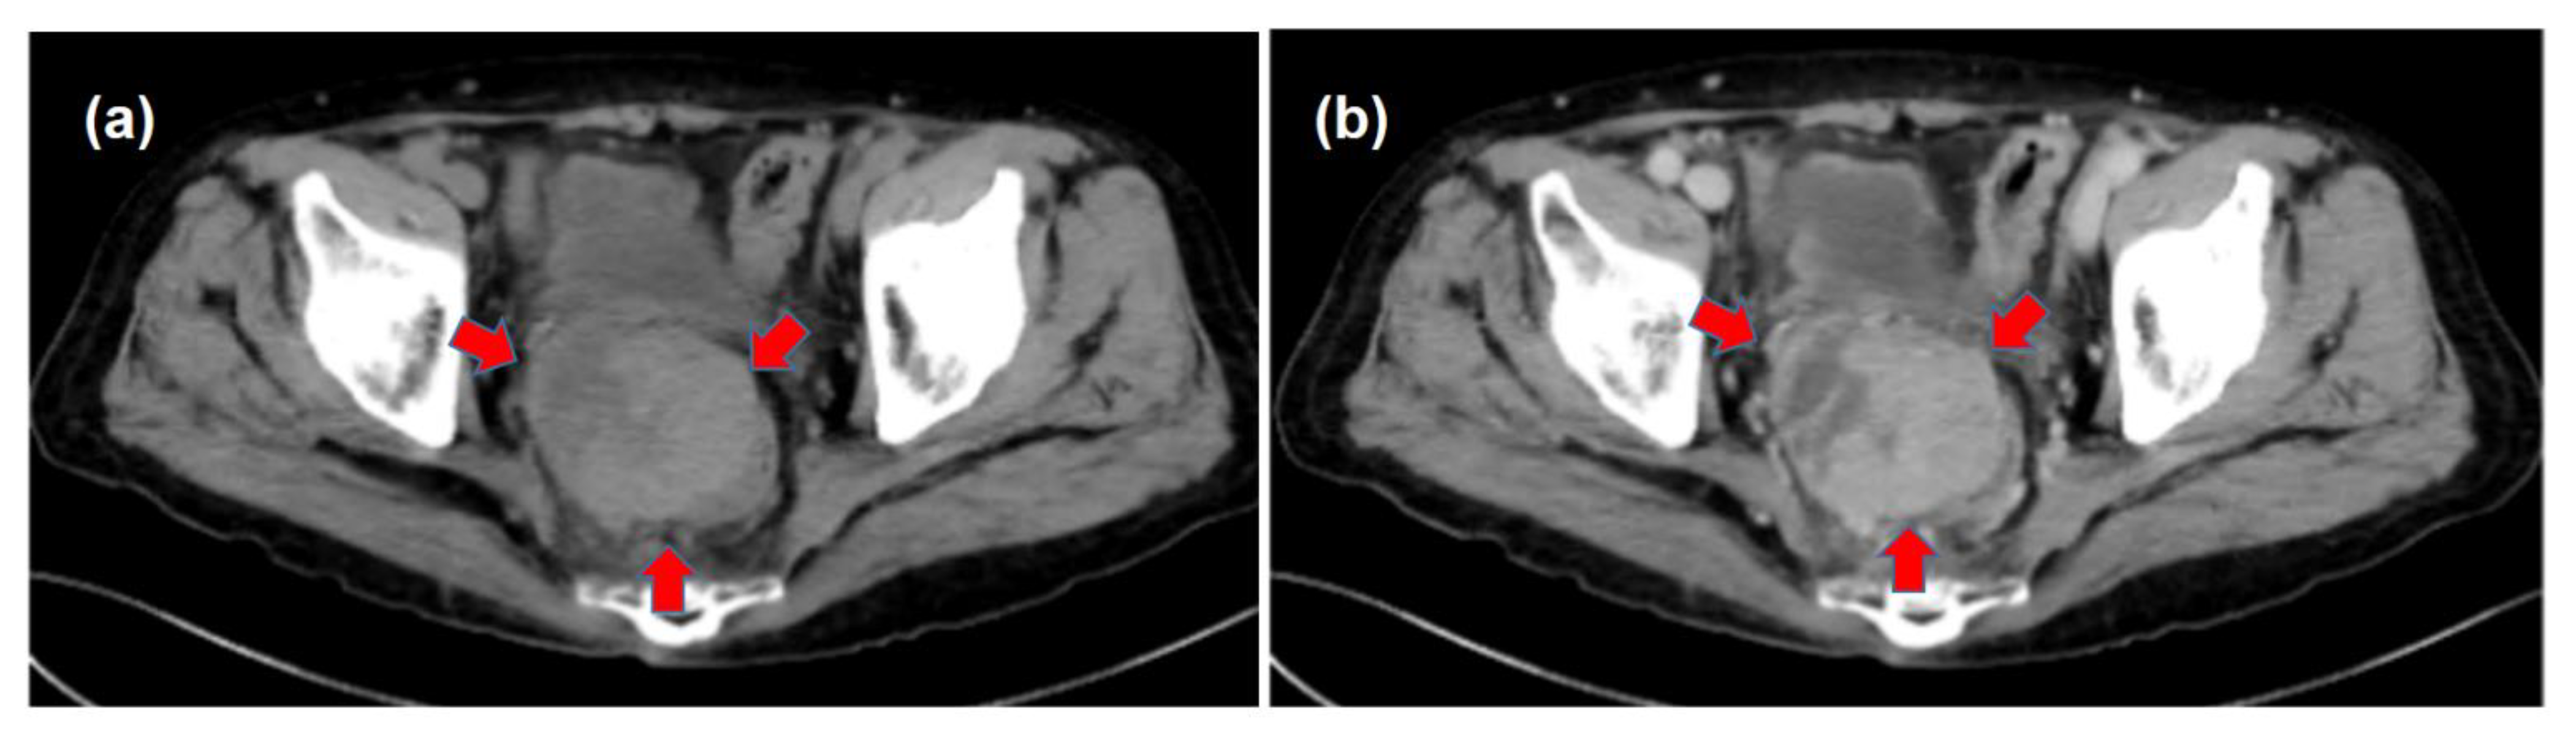

| March | Increase in the DCP and detection of the pelvic tumor Medical interview revealing mild constipation | |

| X | May | The histological diagnosis of pelvic metastasis of HCC |